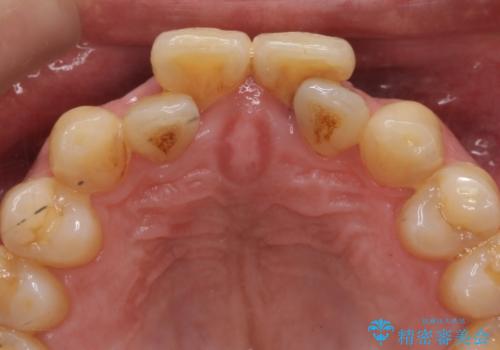

- 前歯の重なったところが虫歯になり、物理的にアプローチが難しい状態でした。

矯正治療前に虫歯を取り、歯並びが良くなってから本格的にセラミック治療を行いました。

左上1はジルコニアクラウン(スペシャル)で治しました。スペシャルの場合は写真をとり、オリジナルの色味で作成することが可能です。